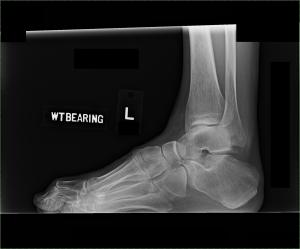

In 2011, I was diagnosed with equinovarus contracture deformity (club foot). This is a result of spasticity, flexor synergies, and internernal rotation. I walk on the side of my foot with my toes clawing the floor, with a high ankle arch, and knee hyperextension since my heel does not touch the ground. I am considering the tendon transfer/ toe fusion surgery. I decided to try a new afo with Botox before doing the surgery. My recovery page has a photo of my latest afo.

If you were to put xray glasses on, this is how equinovarus deformity looks like. Pay special attention to looking through the hole in my ankle bone (the ankle bone is supposed to stack nicely, without holes), clawing toes, rolled foot.